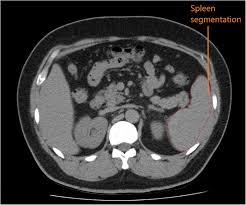

This image is titled back muscles ct anatomy and is attached to our article about best back muscles training exercises. Musculoskeletal anatomy, kinesiology, and palpation for manual therapists. Back muscles are divided into two specific groups: Since learning anatomy is not your primary objective, this is a conceptual view of the the muscles in your upper back are called the trapezius and rhomboids rest underneath your traps. On this page, youll learn about each of these muscles, their locations, and functional anatomy. The spinalis muscle attaches to the spinous processes of the superior thoracic vertebra. Let's remember the back muscles. Fortunately, you don't have to guess. Back muscles rear view & #8211; Tutorials on the anatomy and actions of the back muscles, using interactive animations, diagrams, and illustrations. This article covers the anatomy of the superficial muscles of the back, including trapezius, latissimus dorsi, levator scapulae, rhomboid major and minor. They provide movements of the spine functional anatomy: There are around 650 skeletal muscles within the typical human body.